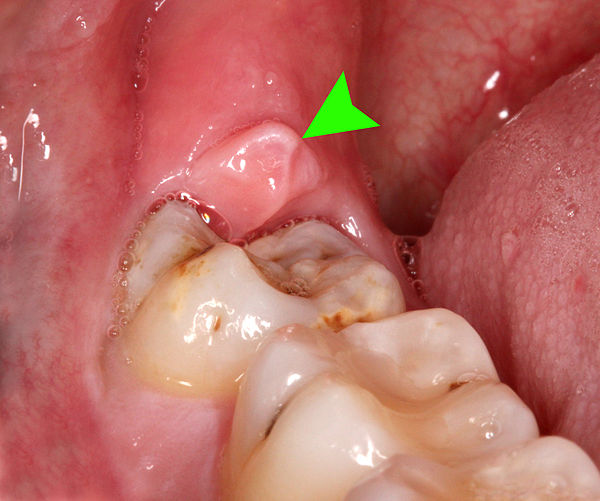

Perikoronitis (peri = sekitar (Yunani), corona = mahkota dan itis = peradangan (Latin)) yang juga dikenal dengan istilah operculitis, adalah peradangan pada jaringan lunak sekitar mahkota gigi yang erupsi sebagian, termasuk gingiva (gusi) dan folikel gigi.

Jaringan lunak meliputi gigi yang erupsi sebagian dikenal sebagai operkulum, daerah yang sulit untuk dicapai saat menyikat gigi dengan metode biasa. Sinonim operkulitis teknis mengacu pada peradangan pada operkulum saja.

Perikoronitis adalah peradangan yang terjadi di dalam mulut akibat infeksi pada jaringan gingiva yang mengelilingi atau menutupi gigi yang sedang erupsi. Kondisi ini paling sering terjadi pada gigi molar ketiga mandibula.